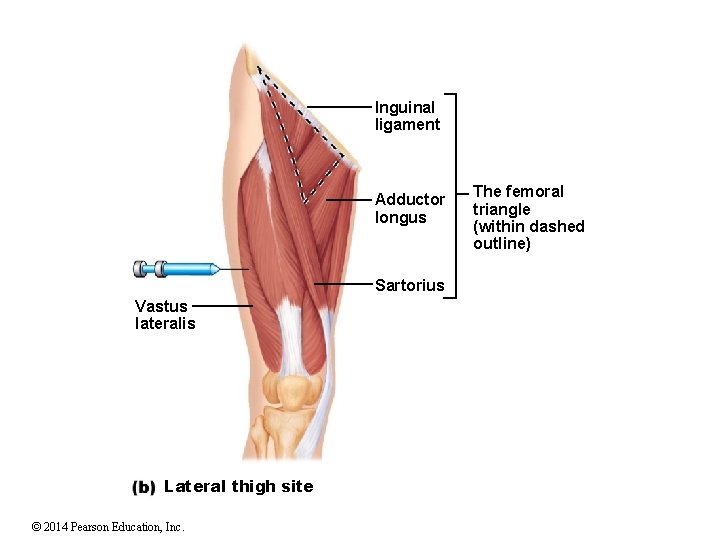

Inguinal ligament Adductor longus Sartorius Vastus lateralis Lateral thigh site © 2014 Pearson Education, Inc. The femoral triangle (within dashed outline)